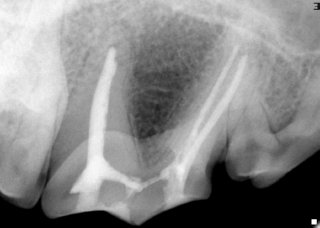

Upper fourth premolar tooth has three roots. Three endodontic files are used to clean out all these roots.

The roots are filled with an inert material.